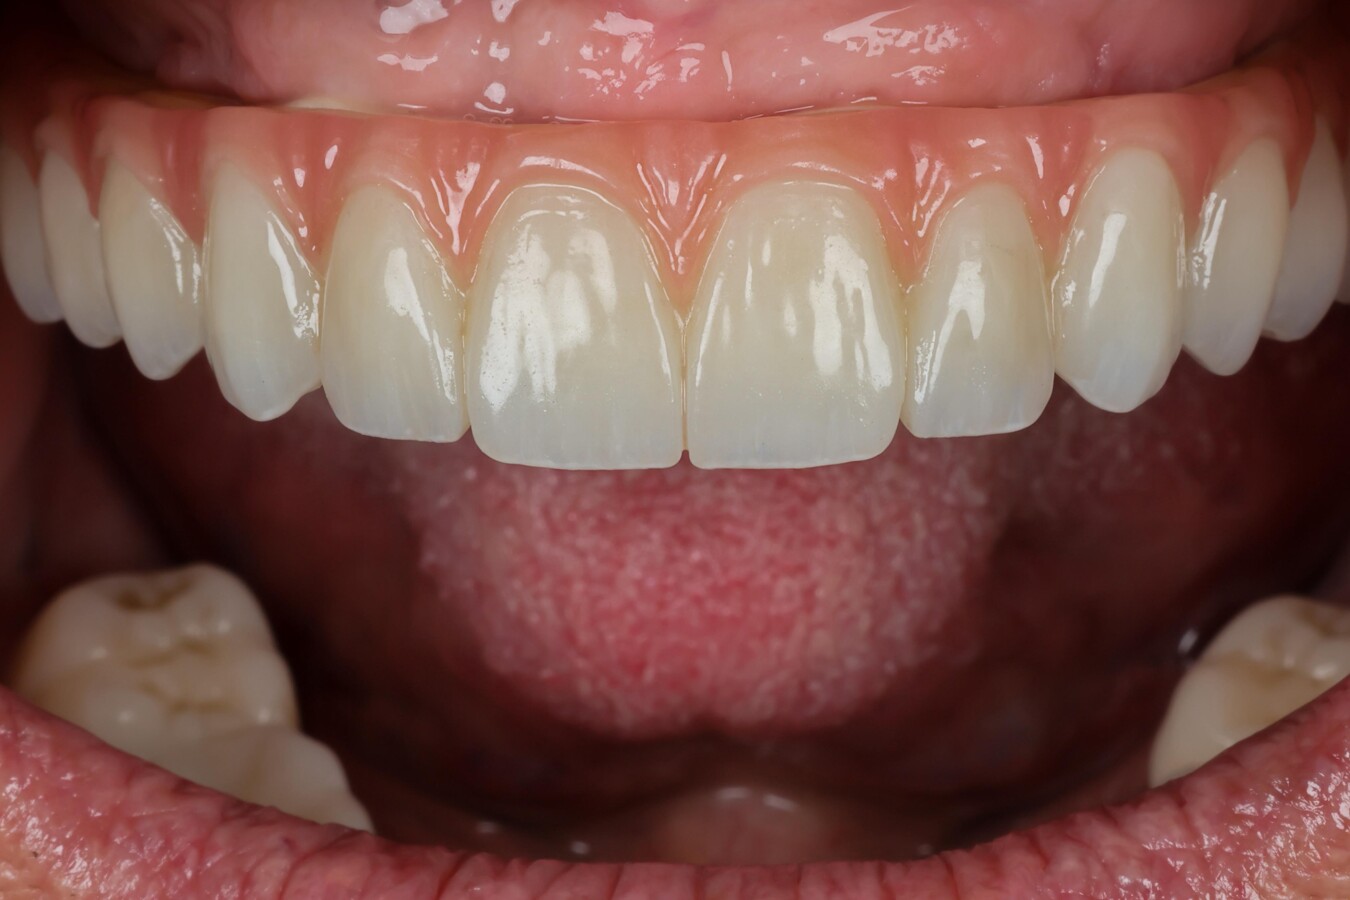

Figura 1. Maxilar superior edéntulo con implantes óseointegrados, caso en el que la posición exacta de los implantes se determinó mediante fotogrametría. (Foto: Camilo Serna)

Figuras 5 y 6. Prótesis híbrida implantosoportada ya colocada en el maxilar superior. Fotos: Camilo Serna